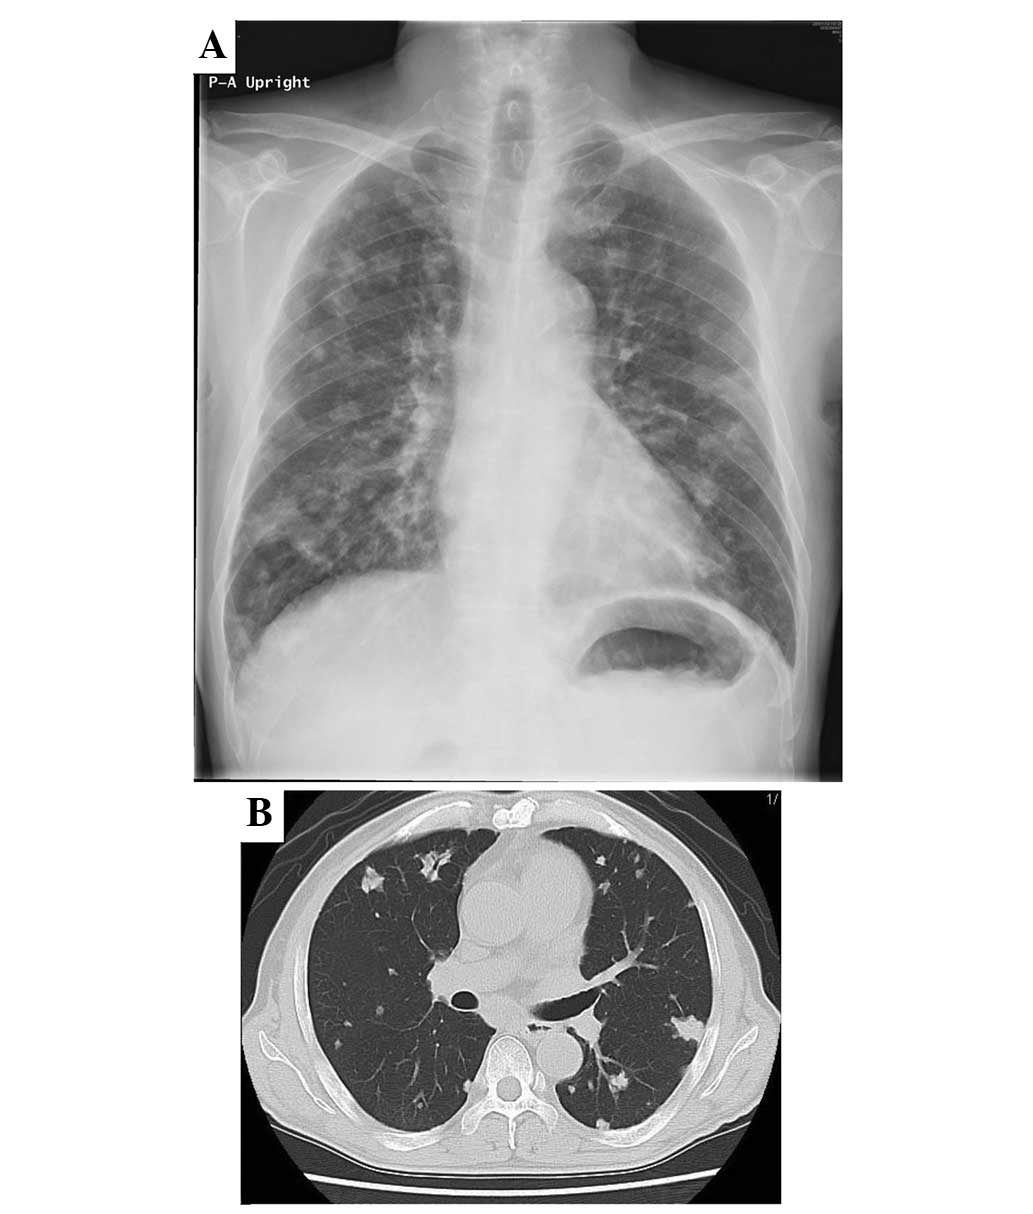

Case report demonstrating effectiveness of sorafenib in multiple lung and bone metastases of renal cell carcinoma

The current study presents the case of a 59‑year‑old male with advanced‑stage renal cell carcinoma and bone metastases in the proximal femur and ilium (cT3aN3M1; stage IV). Resection of the primary renal cell cancer and palliative surgery with a γ‑nail for an impending fracture of the right proximal femur were performed, followed by radiotherapy. Sorafenib, a multi‑kinase inhibitor that blocks the raf and tyrosine kinases of the vascular endothelial and platelet‑derived growth factor receptors, was administered for 9 months, resulting in a marked improvement in the metastatic ilium and a reduction in the extent of the lung metastases. The patient suffered minor adverse effects, including a skin rash and mild diarrhea, but remained alive at the time of follow‑up at 36 months post‑surgery. Sorafenib demonstrated efficacy against the bone metastasis of metastatic renal cell carcinoma.

Figure 1

Figure 2

Figure 3

Figure 4